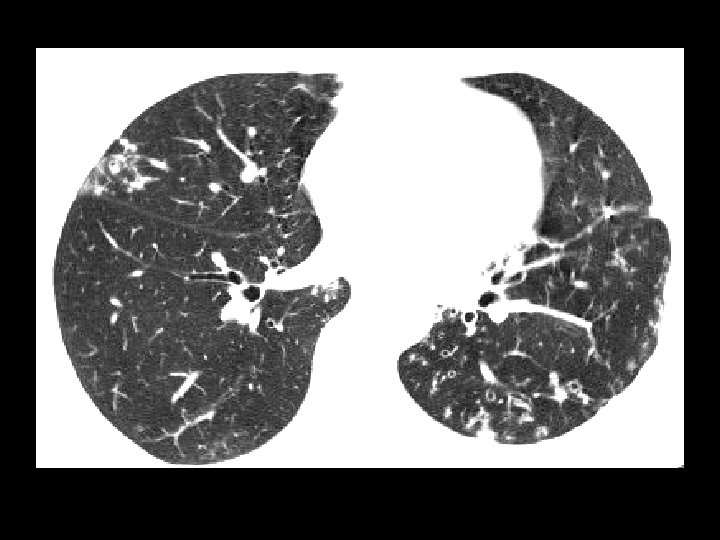

Tuberculosis • Findings: – patchy parenchymal opacities – focal bronchiectasis and accompanying bronchioliltis – bilateral distribution • ddx: – endobronchial spread of tumor